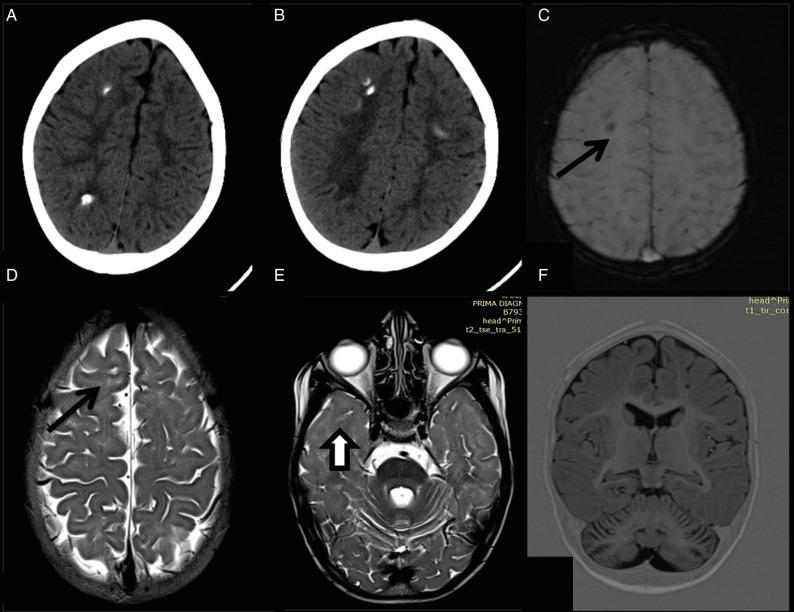

Cerebral folate transport deficiency results from impaired folate transport across the blood:choroid plexus:cerebrospinal fluid (CSF) barrier. This leads to low CSF 5-methyltetrahydrofolate (5MTHF), the active folate metabolite. We are reporting two children with this treatable cerebral folate transport deficiency. Case 1: Seventeen-year-old boy presented with delayed milestones followed by regression, seizures, and intention tremors. On examination child had pyramidal and cerebellar signs. Magnetic resonance imaging (MRI) of brain revealed diffuse cerebral and cerebellar atrophy. Targeted next generation sequencing revealed homozygous missense pathogenic variant in gene in exon 4 c.382C>T p.R128W, confirming the diagnosis of cerebral folate deficiency. Case 2: Six-year-old male child presented with delayed milestones, myoclonic jerks and cognitive regression from 3 years of age. Child had microcephaly with ataxia. Computed tomography (CT) of brain revealed multifocal calcifications. MRI brain revealed cerebellar atrophy with hyperintense T2 signal changes in the subcortical white matter of frontal and temporal lobes. Genetic testing revealed homozygous variant (c.493+2_493+6delTGAGG) in intron 4 of the gene which is a novel pathogenic variant. Both children started on folinic acid and there was a significant improvement in development, behavior, ataxia, and decrease in seizure frequency. In conclusion, cerebral folate transport deficiency should be suspected in every child with global developmental delay, epilepsy, ataxia and neuroimaging showing cerebellar atrophy and calcification. Response to folinic acid supplementation is partial if diagnosed late and treatment initiation is delayed.